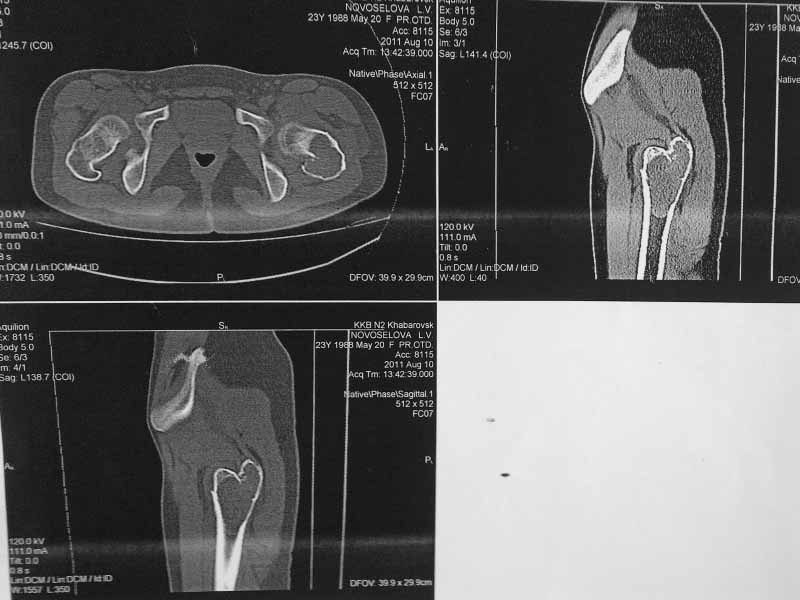

Молодая пациентка 23 лет. Травма в результате падения с высоты своего роста.

Упала 2 дня назад доставлена к нам вот с такой картиной. Из анамнеза - боли беспокоят в течении полугода, постоянные. Никуда не обращалась. Уважаемое сообщество подскажите - ОБК?, Фиброзная дисплазия?, Киста?. Тактика ведения?. Девушка молодая!!!